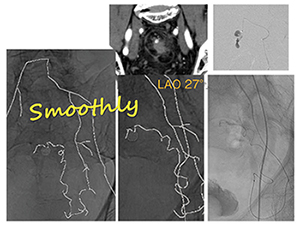

図2は、術後に直腸断端に仮性動脈瘤が認められた症例で、左の内腸骨動脈末梢の蛇行した血管の先に出血部分が認められた。手技を行うに当たって仮想透視画像を作成し、蛇行血管のカーブの形状を把握しやすいCアームのワーキングアングルを検討したところ、LAO27°が最適と思われた。実際にその角度での血管走行を把握して手技を行ったところ、スムーズにカテーテルを進めることができた。仮想透視画像は3Dデータであり、画像上で任意の角度に振ることができるため、どの角度で見れば最も手技を行いやすいかを術前に把握して実際の手技に臨むことができる。また、骨だけではなくドレーンやチューブ、ステープラーやパッキングされたガーゼなども透視と同様に表示されるため、それらを目安にして手技に生かすこともできるのがメリットである。

図2 術後直腸断端仮性動脈瘤症例

内腸骨動脈の末梢の出血に対して蛇行した血管走行が見やすいワーキングアングルを把握して手技ができる。